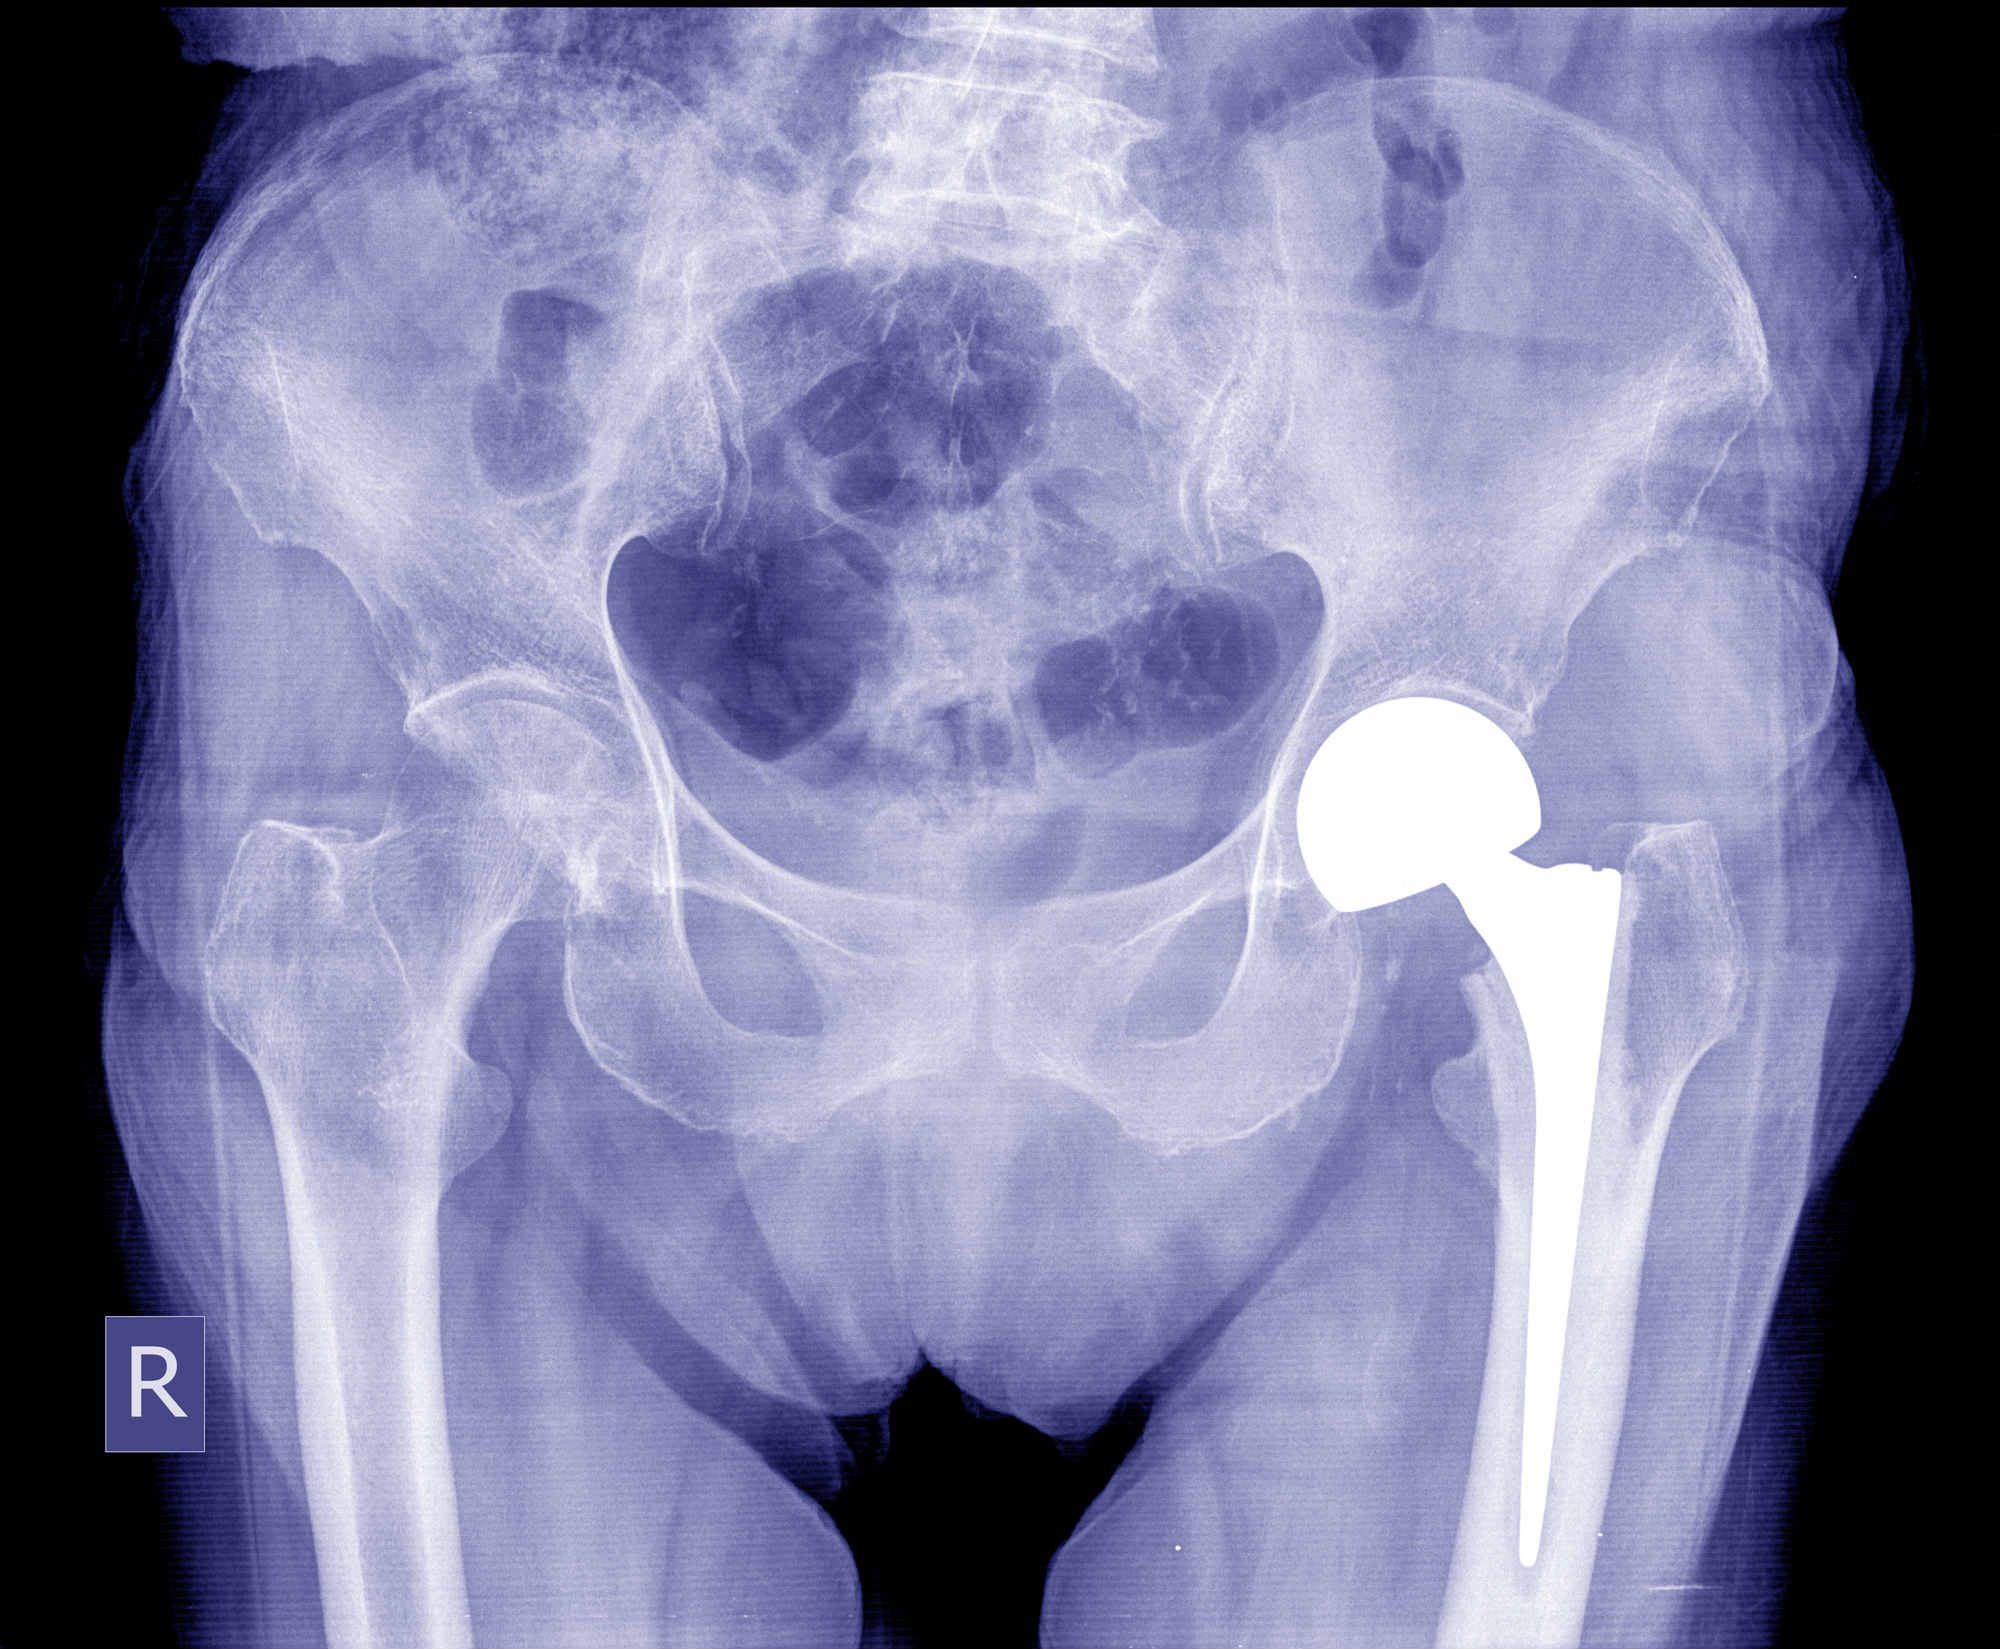

Stryker LFIT V40 Failure Common With Howmedica Hip Replacement, Lawsuit ClaimsStryker Medical Devices thought they had produced a revolutionary metal hip implant that was sturdier, more reliable and lasted longer than older plastic models — or at least that’s how they marketed the device. Diana Jaras was one of the many hip implant victims who opted for a Stryker device before the implant was recalled by the manufacturers just a few years after it was released. For her, the Stryker hip implant nearly cost her life.

In 2012, Stryker recalled two defective metal-on-metal hip implants: the Stryker Rejuvenate and ABG II systems. It’s estimated that 20,000 people had a Stryker hip implant inserted between 2007 and 2012, which comes with a titanium stem and cobalt neck. Both titanium and cobalt are usually fine by themselves, but working together they can become toxic. The two metals have a tendency to rub together, flaking off bits of combined metal into the body’s system. Many people report negative reactions to the mixture, and the titanium has been found to get into the bloodstream — sometimes at toxic levels.